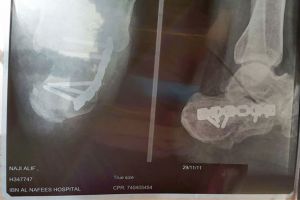

ومثل المتهم أمام المحكمة أمس في جلسة التجديد، وعندما سأله القاضي: هل قتلت المجني عليه؟ قال: نعم، فسأله القاضي : لماذا قتلته، أجاب بلا تردد: كان يزعجني كثيرا. تشير المعلومات إلى أن القتيل في العقد الخامس من عمره ويعمل في إحدى الشركات، ويسكن في سكن العمال، وقد اكتشف زميله جثته مضرجة بالدماء بعد عودته من العمل يوم 17 مايو/ أيار 2015، وانتقلت الشرطة وفريق مسرح الجريمة إلى المكان وبعد المعاينة، تبين أن المجني عليه قتل بعد إصابته بأربع طعنات في العنق وطعنة في البطن غير حيوية، وقطع في عضوه الذكري، ومن الخلف سبع طعنات بالظهر وجرحين قطعيين بالعنق، وطعنة بالعضد الأيمن.